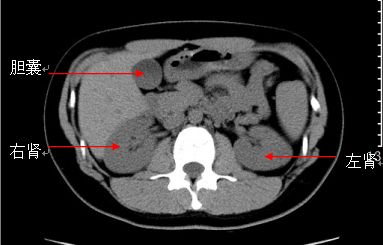

2)正常CT表现:肝实质密度均匀,未见异常密度灶。胆囊不大,未见高密度灶。胰腺形态如常。脾不大,密度均匀。两肾形态位置正常,未见明显异常密度影。